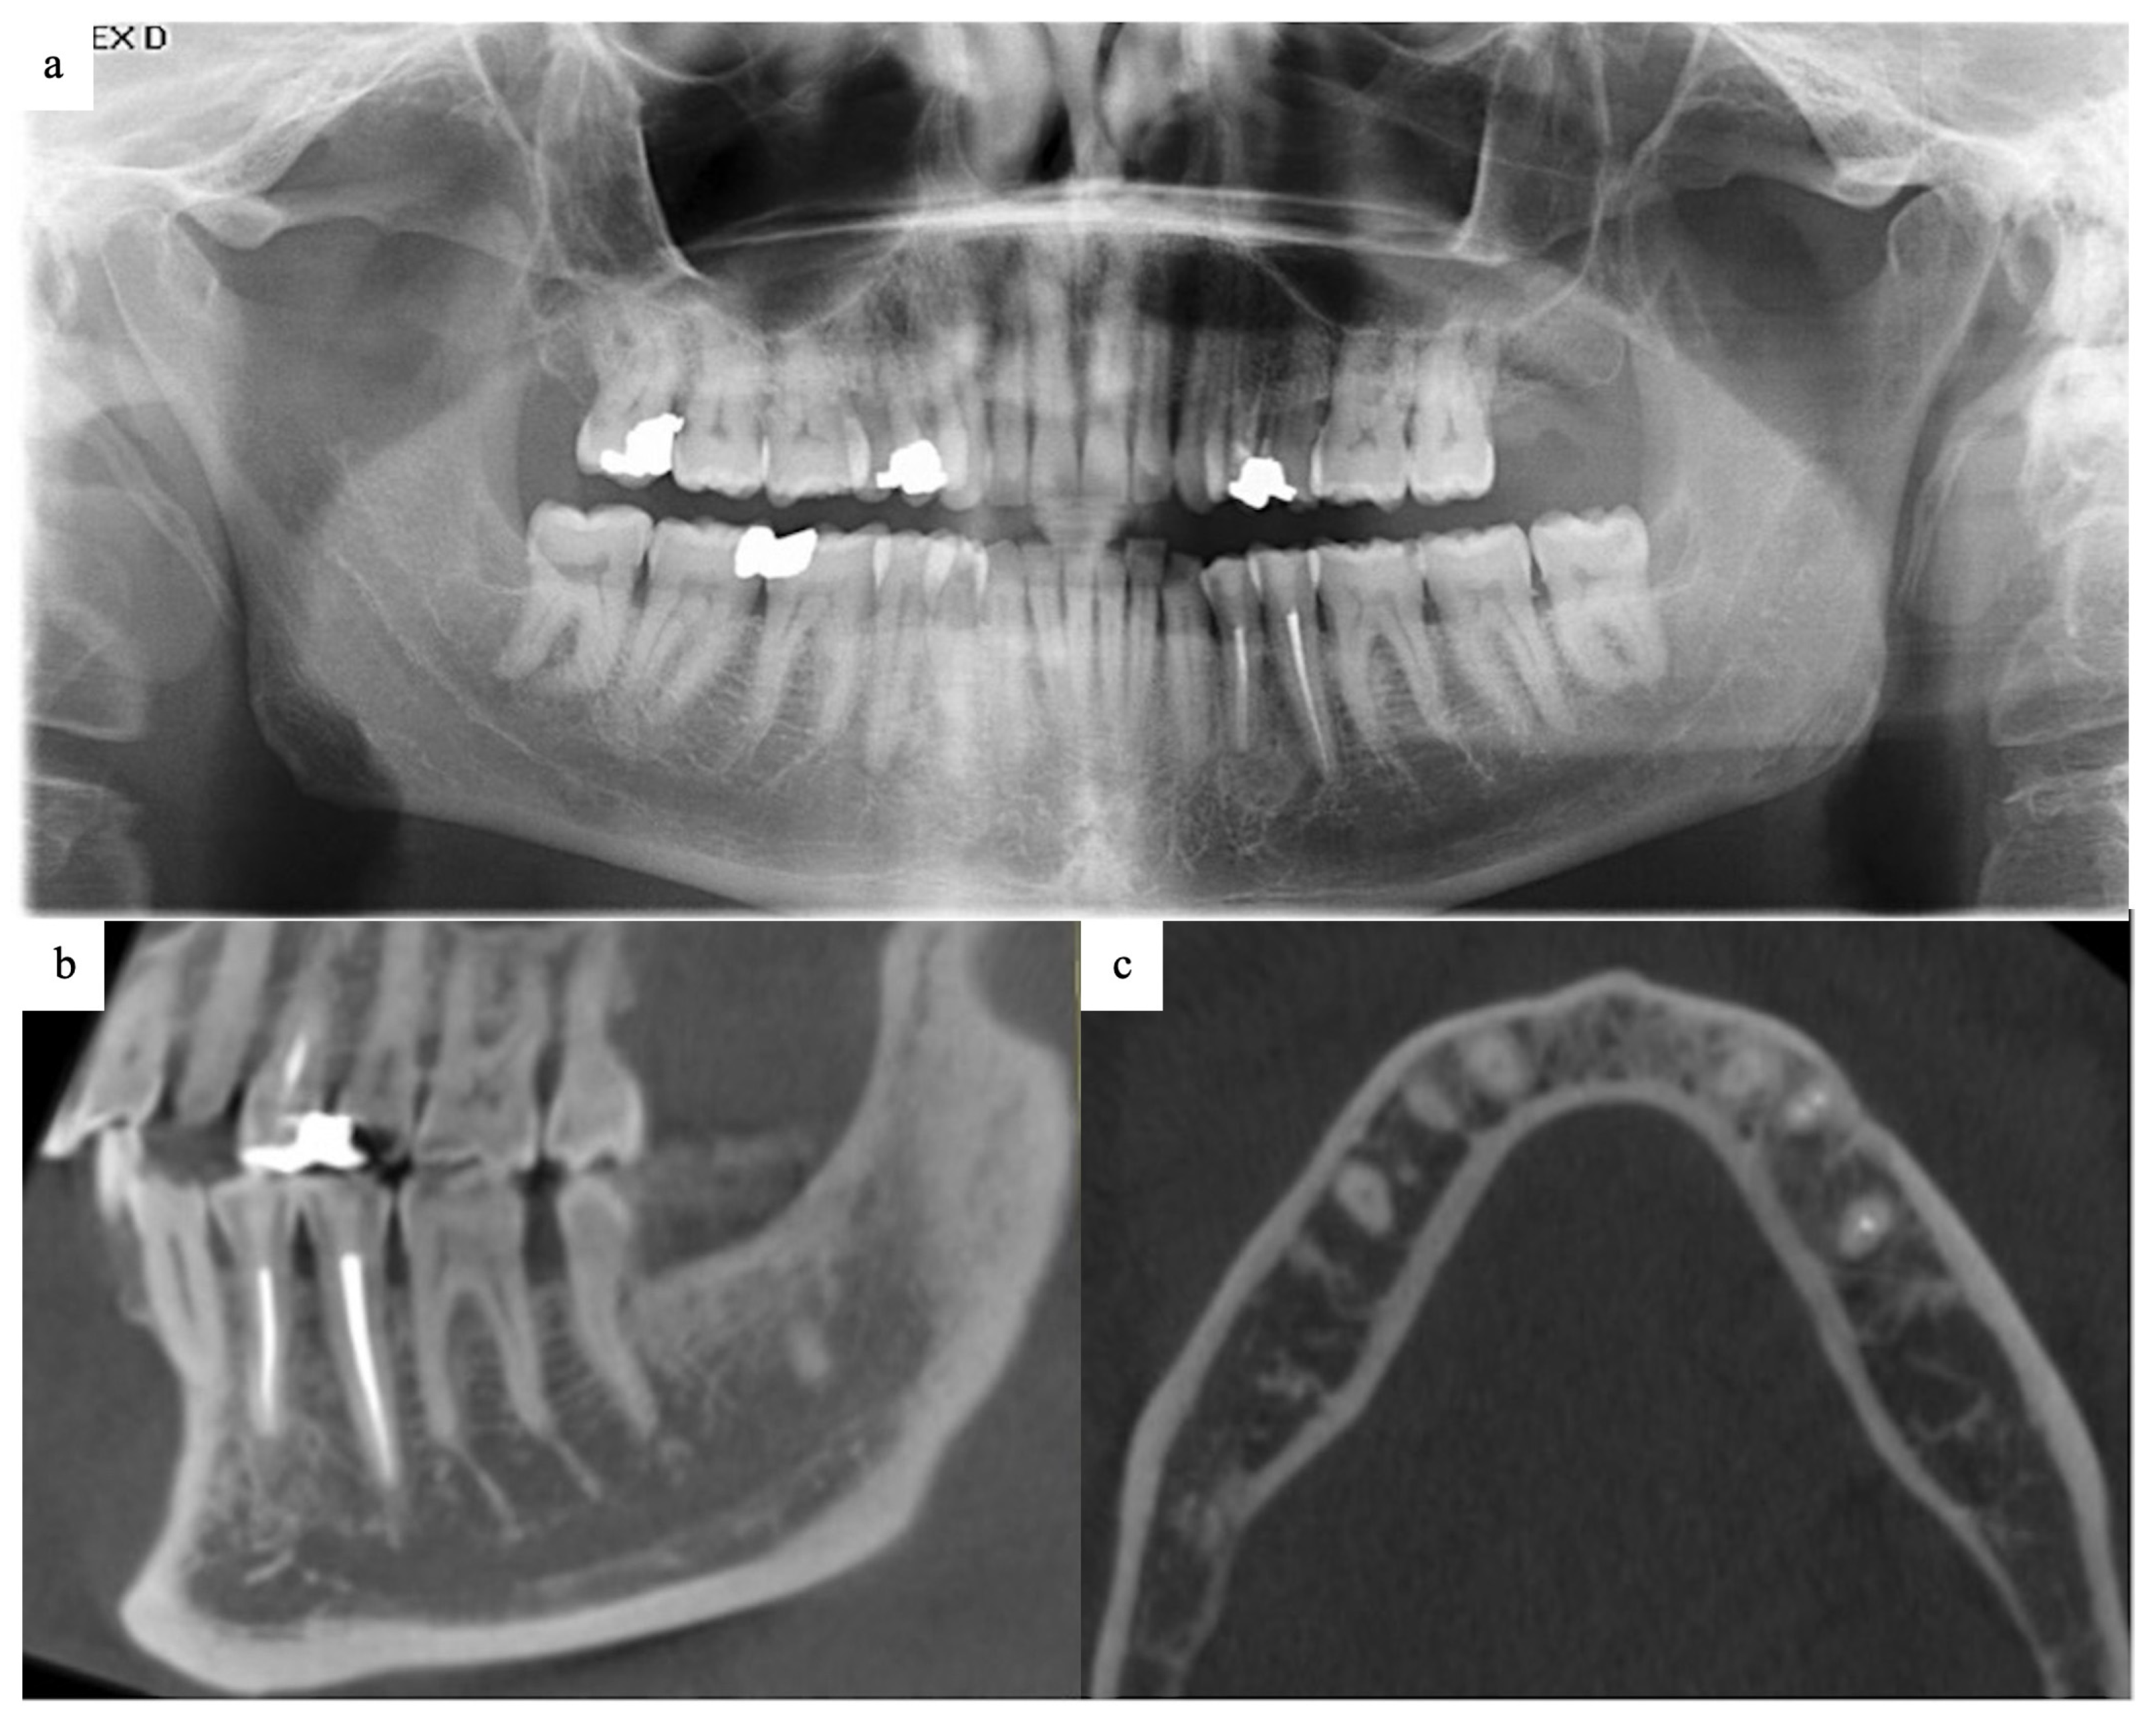

2.1. History and Examination